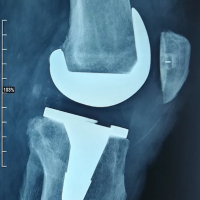

PROTHÈSE DU GENOU (PTG) L’arthrose du genou est une maladie fréquente qui touche plus d’une personne sur quatre après 65 ans. Elle entraine une destruction progressive du cartilage articulaire du genou. L’usure du cartilage s’accompagne d’une dégradation des ménisques, des muscles ainsi que d’une inflammation synoviale. Il s’agit d’une atteinte globale de l’articulation qui devient douloureuse et commence à s’enraidir....